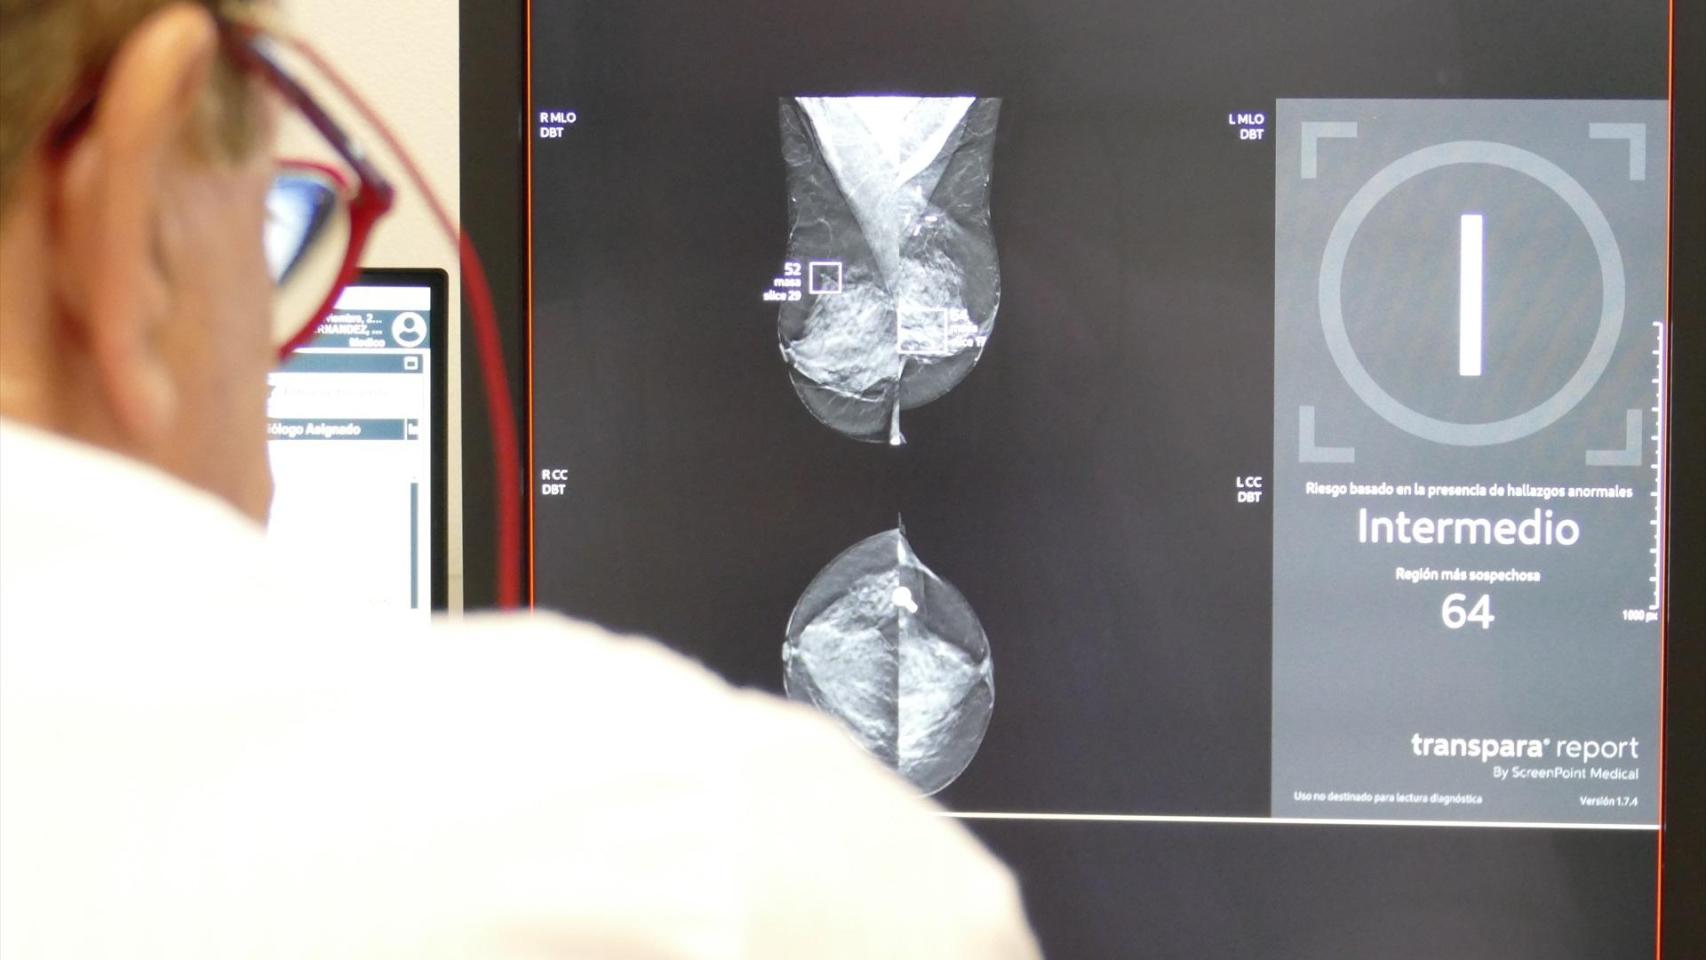

Consecuencia de esta crisis del cribado de cáncer de mama fue la dimisión de la consejera de Salud, Rocío Hernández. A eso siguió el anuncio por parte del presidente de la Junta de una nueva unidad de cáncer de mama y otra de cáncer de colon en el hospital Muñoz Cariñanos de la capital hispalense. También el uso de Inteligencia Artificial en el sistema sanitario de Andalucía para detectar casos de cáncer.